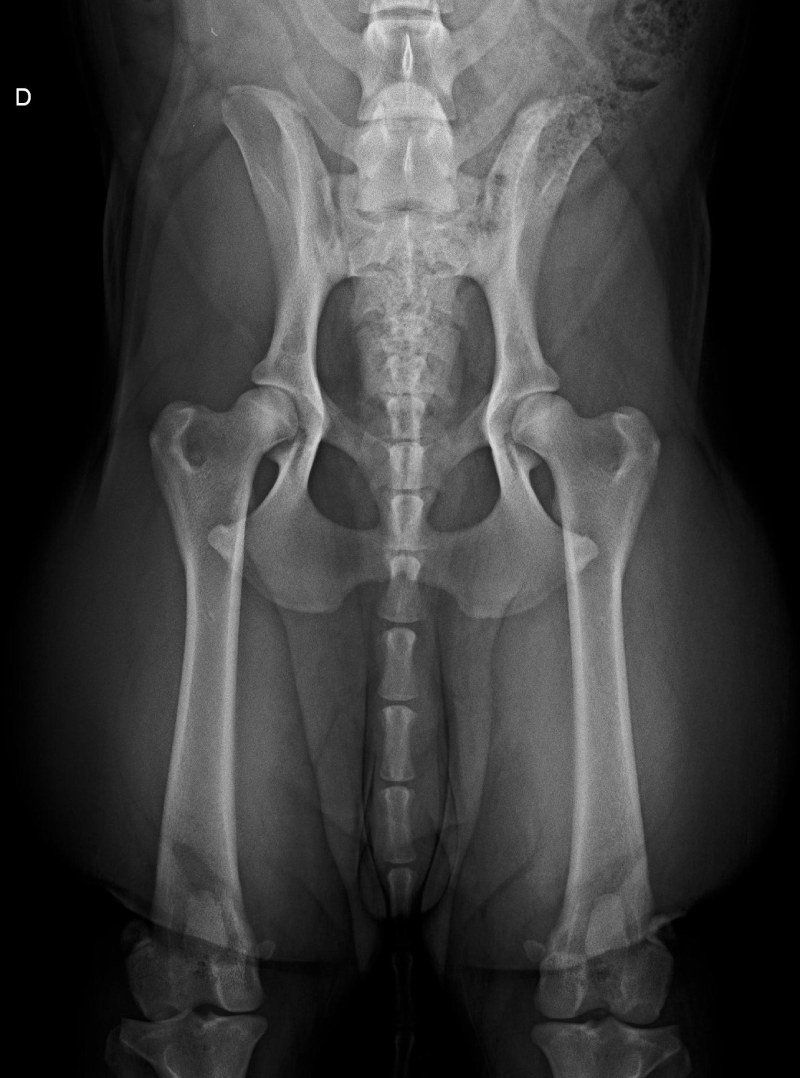

Offriamo i servizi che solo dei veri professionisti seri e qualificati del settore possono assicurare, così che i tuoi amici a quattro zampe possano godere sempre di buona salute. Ci occupiamo anche di eseguire studi radiografici ufficiali per le patologie scheletriche ereditarie, come ad esempio la displasia dell'anca o del gomito.